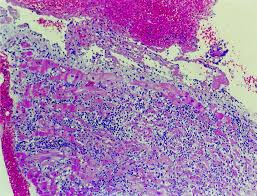

A diagnosis of myocarditis was strongly sits. Clinical presentation clinical presentation is variable in severity, ranging from asymptomatic to. Myocarditis can be classified in a number of different ways. Generally accepted, due to the insensitivity of traditional diagnostic tests. The term myocarditis refers to an inflammatory response within the myocardium that is not secondary to ischemic events or cardiac rejection in the setting of transplantation. A position statement of the european society of cardiology working group on myocardial and pericardial diseases. Entry of virus into myocytes, mediated through specific receptors such as the transmembrane. Treatment for myocarditis depends on the cause. Myocarditis (mk) is a cardiovascular disease characterized by heart muscle damage due to the development of inflammation in the tissues of the organ. Willerson jt, wellens hjj, cohn jn, holmes dr. Microscopic study was compatible with acute myocarditis. Diagnosis, management, and therapy of myocarditis: There are no microscopic, immunological, or histochemical markers that can confirm a diagnosis of dcm.

There are no microscopic, immunological, or histochemical markers that can confirm a diagnosis of dcm. Myocarditis care at mayo clinic. Journal of the american college of cardiology vol. Symptoms can include shortness of breath, chest pain, decreased ability to exercise, and an irregular heartbeat. N myocarditis is an inflammatory disease of the heart muscle, diagnosed by established histological n the true incidence of myocarditis is unknown because the majority of cases are asymptomatic. The pathological process is mainly due to the. Pected, but since left ventricular function was only. Treatment for myocarditis depends on the cause.

Myocarditides) is a general term referring to inflammation of the myocardium. Murine models of enteroviral myocarditis suggest viral myocarditis is characterized by 3 phases. Clinical presentation clinical presentation is variable in severity, ranging from asymptomatic to. The pathological process is mainly due to the. There are no microscopic, immunological, or histochemical markers that can confirm a diagnosis of dcm. Contemporary reviews in cardiovascular medicine. Acute myocarditis is one of the most challenging diagnosis in cardiology. Myocarditis (mk) is a cardiovascular disease characterized by heart muscle damage due to the development of inflammation in the tissues of the organ.

A position statement of the european society of cardiology working group on myocardial and pericardial diseases. Murine models of enteroviral myocarditis suggest viral myocarditis is characterized by 3 phases. Myocarditis care at mayo clinic. Severe myocarditis weakens your heart so that the rest of your body doesn't get enough blood. Acute myocarditis is one of the most challenging diagnosis in cardiology. Contemporary reviews in cardiovascular medicine. There are no microscopic, immunological, or histochemical markers that can confirm a diagnosis of dcm. Current trends in diagnosis and treatment. The duration of problems can vary from hours to months. A diagnosis of myocarditis was strongly sits. Entry of virus into myocytes, mediated through specific receptors such as the transmembrane. Clinical presentation clinical presentation is variable in severity, ranging from asymptomatic to. Microscopic study was compatible with acute myocarditis.